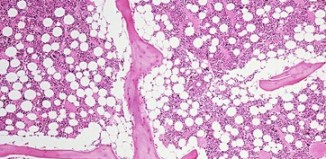

Necrotizing Enterocolitis In infants, the most common gastrointestinal medical emergency is necrotizing enterocolitis or NEC. NEC is a life-threatening disorder which is caused by inflammation...